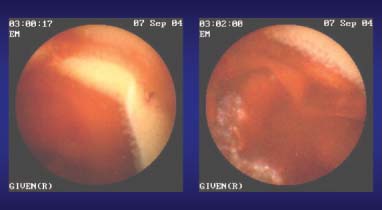

Hinsichtlich der Wertigkeit der Kapsel bei obskuren GI-Blutungen verfügen wir bisher erst über eine grössere prospektive Studie die von Pennazio im Sommer dieses Jahres in Gastroenterology publiziert wurde [9]. Die Sensitivität für das Auffinden obskurer GI-Blutungen lag hier bei 88.9%, die Spezifität bei 95%. Über die Hälfte der eindeutig pathologischen Befunde waren Angiodysplasien des Dünndarms. Allerdings zeigte sich auch, dass die Trefferquote mit zunehmender zeitlicher Distanz vom Blutungsereignis abnimmt. Wenn die Blutung mehr als vier Wochen zurückliegt ist auch die Ausbeute der Kapselendoskopie fast Null.

Aktive Blutung im Bereich des Dünndarms: